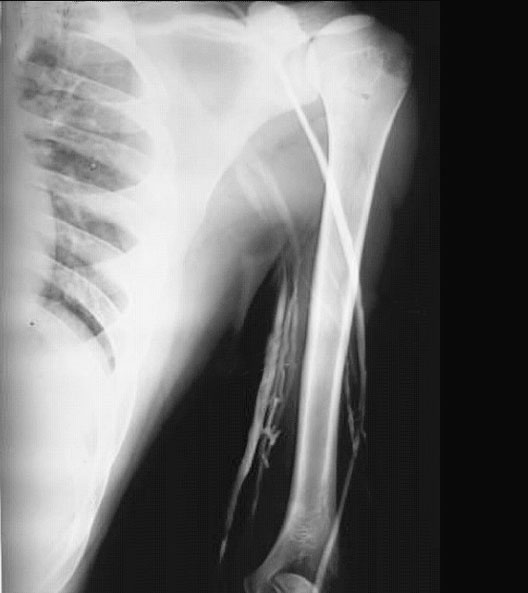

Upper Limb Venogram

1. Cephalic Vein

2. Brachial Veins